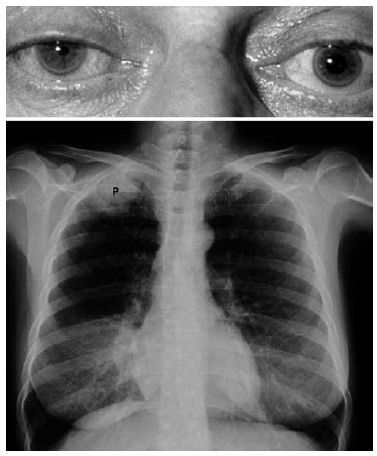

Mulher de 71 anos, tabagista (50 anos/maço), apresenta tosse produtiva, dor torácica à direita e em membro superior direito de caráter neuropático há um mês. Realizado RX tórax (imagem da fáscies da paciente e RX a seguir).

Diante do exposto, é correto dizer que a paciente apresenta